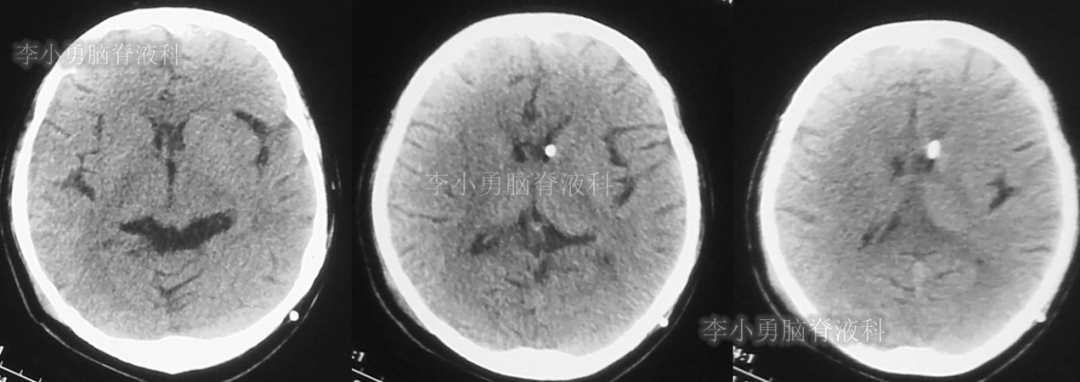

入院时(2020年2月21日)头颅CT(图-22)见脑室缩小,呈裂隙状。

图-22:2020年2月21日头颅CT